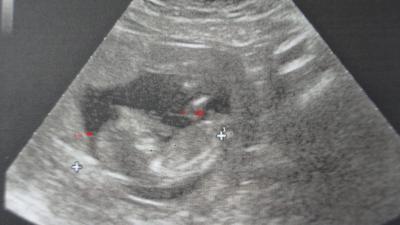

Ein Foto von unserem Zwergal :)

Hello, war gestern beim Schilddrüsen-Dok und er hat auch unserer Zwergal angschaut :) Und er meinte es könnte ein Junge sein :) Da mein TSH Wert auch immer zu hoch war ( bei 3) hat er ganz genau gschaut aber es ist gut gewachsen :) Ich versteh die Krankenhäuser und Kassenärzte in Ö nicht, die kennen sich gar nicht aus! Hab im Schilddrüseninstitut im Kh immer gsagt,ghört mein Wert nicht bei 1 und die meinten nö 3 passt eh, obwohl der private Doktor gestern bestätigte das der Wert bei 1 sein soll!! Bin froh, das mein Zwergi keinen Schaden gnommen hat :) Lg Manuela + Zwergi